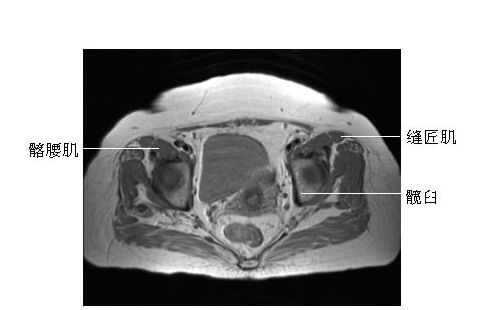

髋关节横断面-MRI图